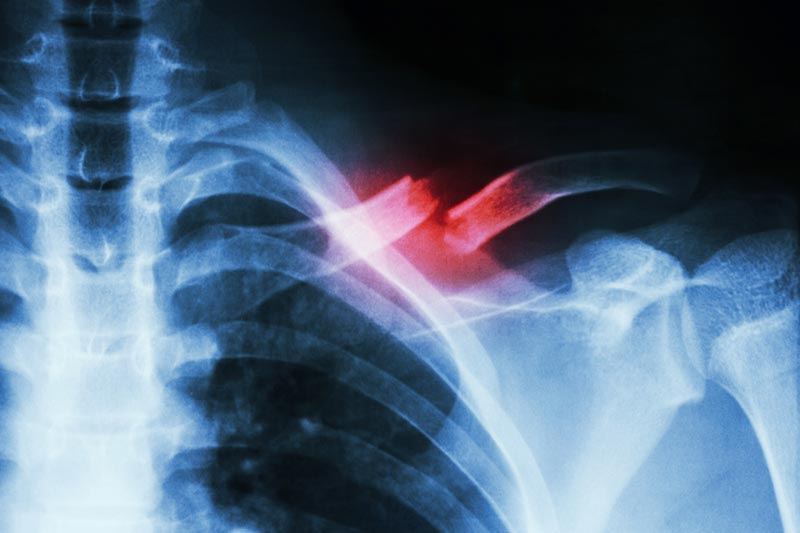

A clavícula, também conhecida como osso da saboneteira, é uma estrutura importante do corpo humano, localizada na parte superior do tórax, que desempenha um papel fundamental na mobilidade do ombro e na estabilidade...